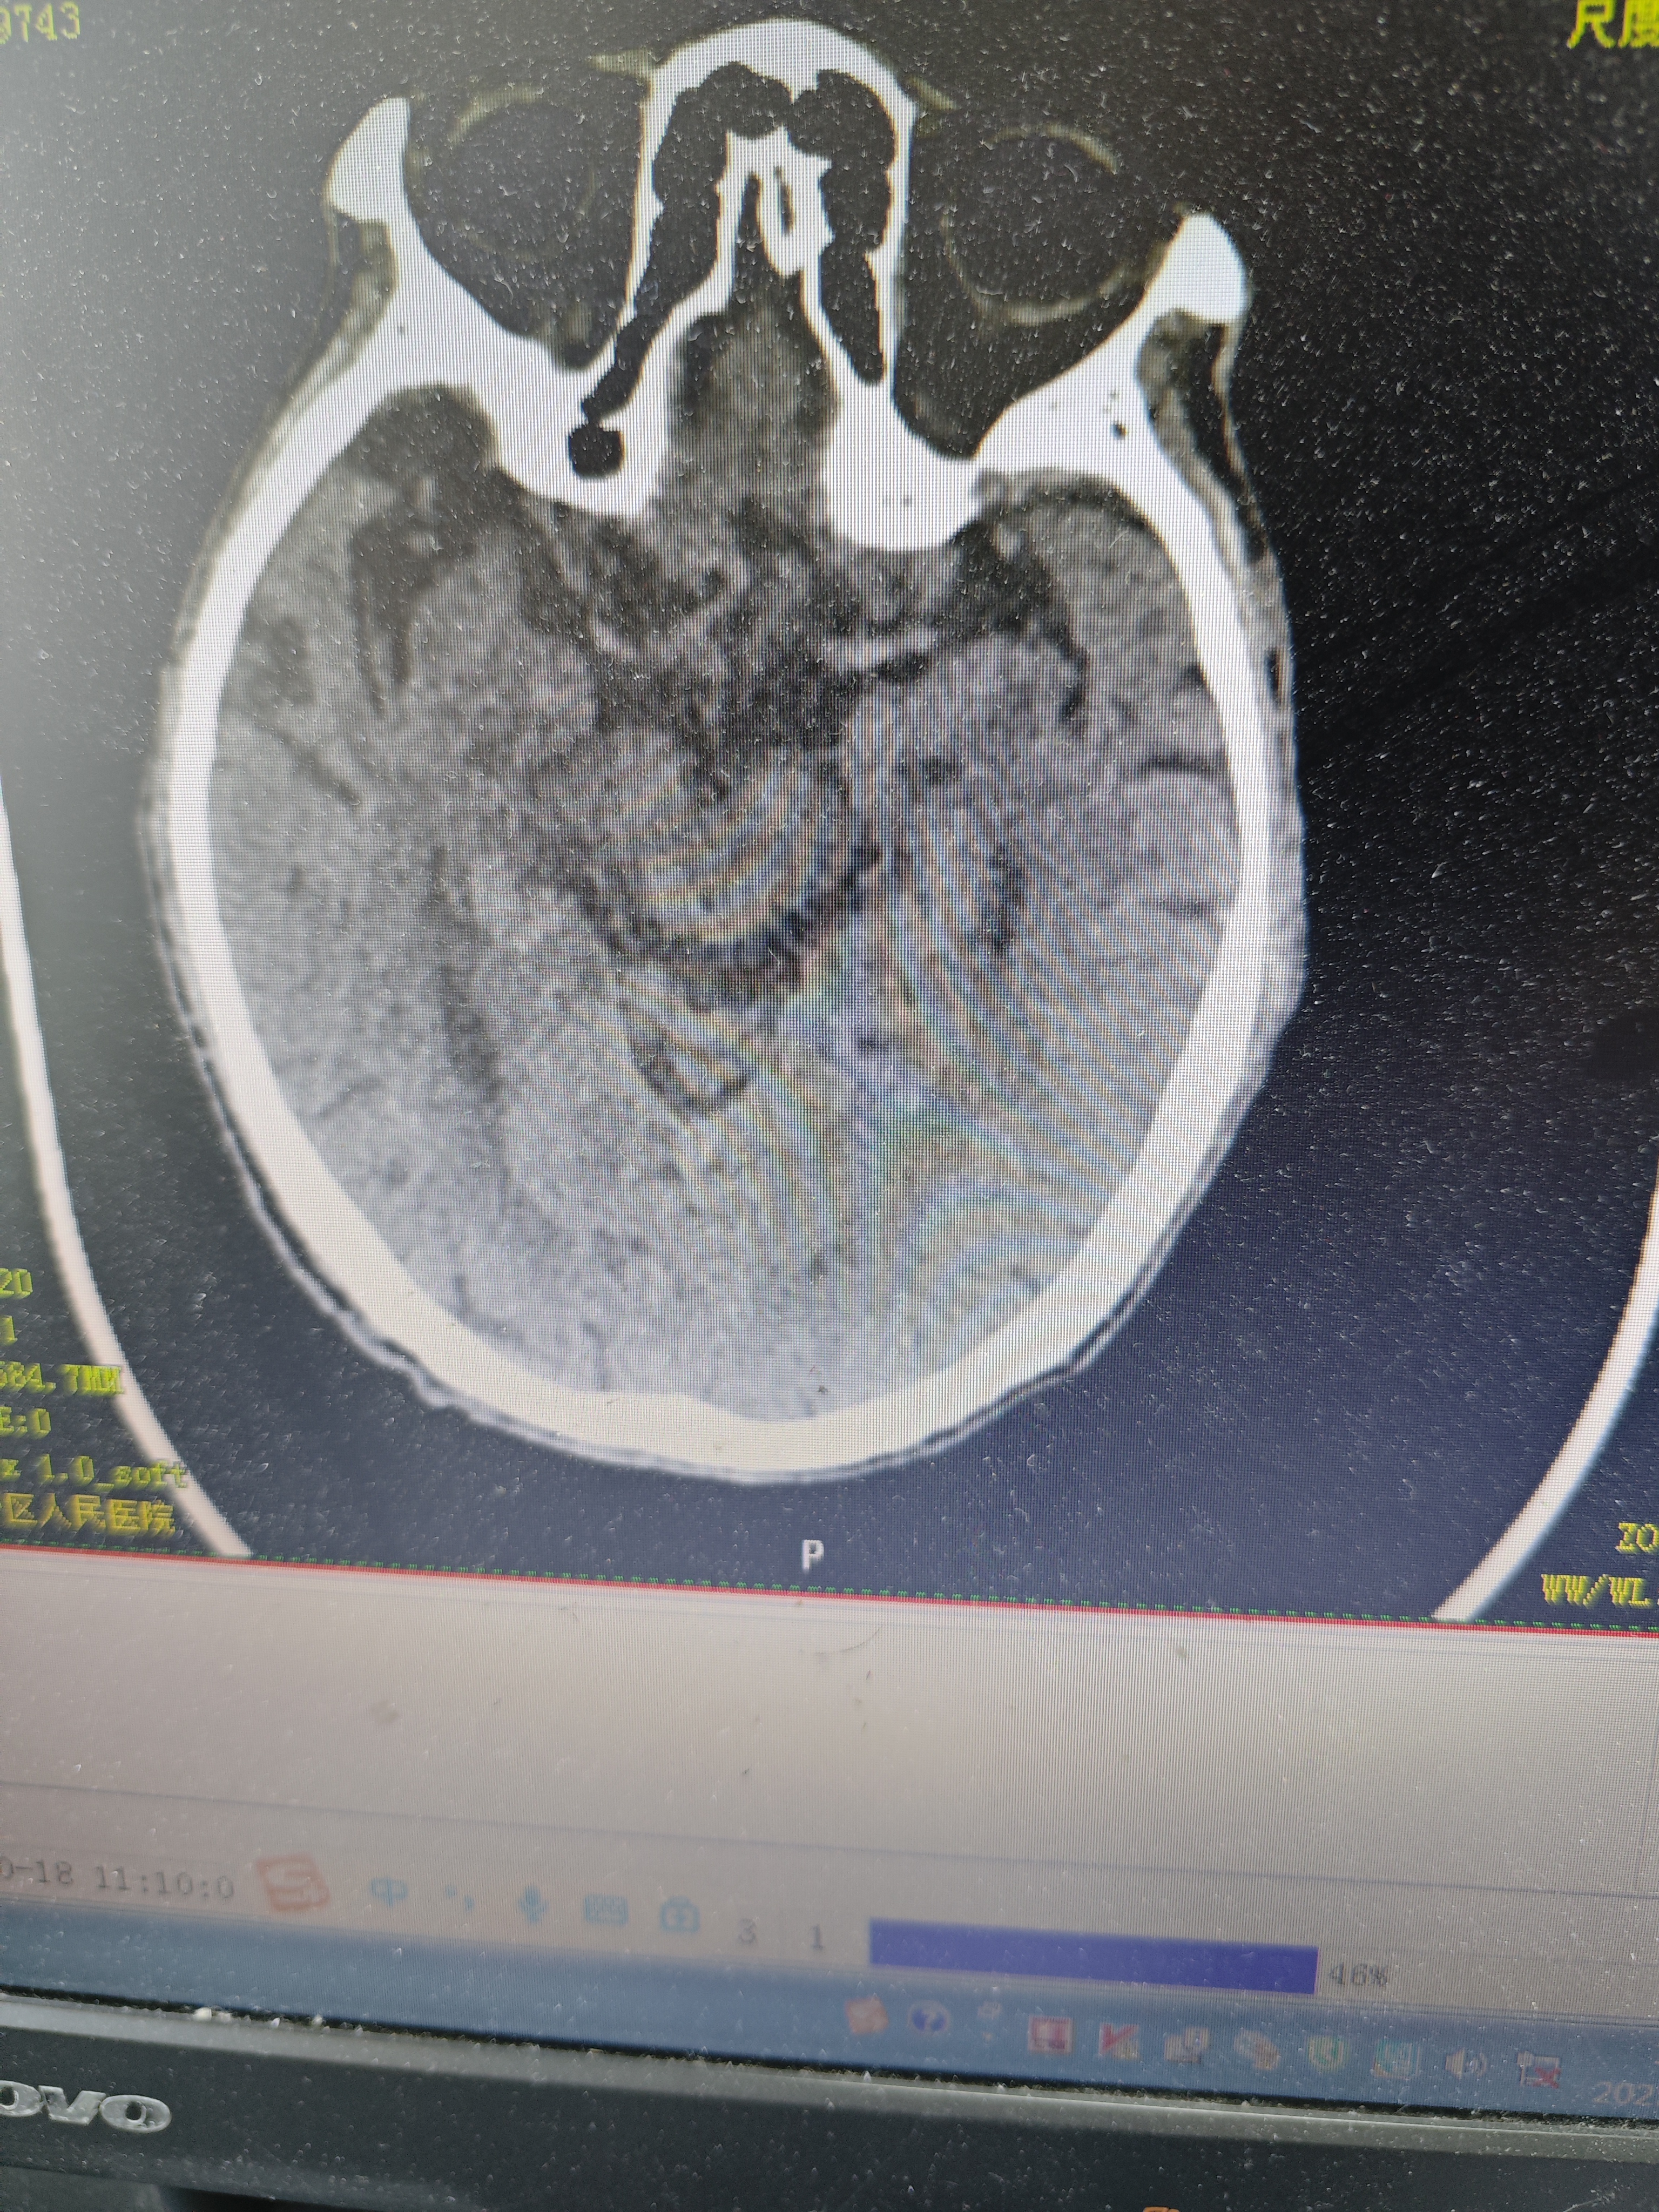

· 看不见的伤:去医院拍CT或磁共振,通常查不出任何结构损伤(比如出血或裂开)。它伤的是“功能”,不是“结构”。

如果出现以下任何一个信号,说明可能不只是简单的脑震荡,可能存在更危险的颅内出血或损伤,必须立即拨打急救电话!